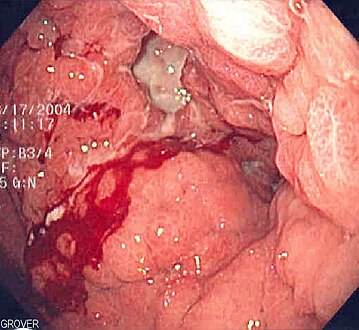

Endoscopic image of linitis plastica, where the entire stomach is invaded with stomach cancer, leading to a leather bottle like appearance

Linitis plastica is a widely used term for Brinton's disease (also known as leather bottle stomach), a morphological variant of diffuse (or infiltrating) stomach cancer. In some texts, the term is also used to describe the condition of a rigid, non-distensible stomach which may be caused by a non-malignant condition such as a caustic injury to the stomach.

Linitis plastica is a type of adenocarcinoma and accounts for 3–19% of gastric adenocarcinomas.[1] Causes of cancerous linitis plastica are commonly primary gastric cancer, but in rarer cases could be metastatic infiltration of the stomach, particularly breast and lung carcinoma.[2] It is not associated with H. pylori infection or chronic gastritis. The risk factors are undefined, except for rare inherited mutations in E-cadherin. The hereditary form of this cancer, hereditary diffuse gastric cancer, accounts for only 1–3% of gastric adenocarcinomas. Somatic mutations in this gene are found in about 50% of diffuse-type gastric carcinomas.[2]